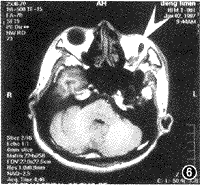

腦積水影像4腦寄生蟲病

腦寄生蟲病可發生於任何年齡,有腦囊蟲,包蟲以及肺吸蟲病,多為外來感染,它可侵犯人體多個部位,由於感染部位,蟲體及個體免疫差異,其症狀多樣,臨床上以癲癇型最多見,癲癇發作結合典型的%&`片診斷不難,但由於病變的複雜性,往往造成誤診,腦寄生蟲病的臨床表現主要取決於蟲體的寄生位置,範圍,數量,周圍組織反應的改變,血液循環及腦脊液循環障礙的程度,有的表現象顱內占位性病變,有的酷似多發性硬化,腦炎,給診斷帶來一定困難,頭顱%&可以確定病變部位,大小,數量,並能顯示腦積水或腦萎縮及形態改變,對於不典型患者應結合免疫學試驗,給予診斷性治療。